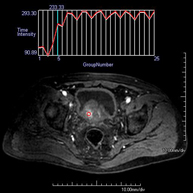

Prova diagnòstica no invasiva que consisteix en l'obtenció d'imatges d'alta definició anatòmica de la glàndula prostàtica mitjançant l'ús d'un camp electromagnètic i ones de ràdio (amb un emissor i un receptor). No utilitza radiació ionitzant. S'utilitza una bobina endorectal per obtenir imatges de màxima definició anatòmica de la pròstata i permetre fer l'estudi espectroscòpic (estudi a nivell molecular que ajuda a diferenciar les cèl·lules d'origen maligne o tumoral). També es realitza l'estudi amb contrast paramagnètic, que aporta una millor definició tissular. Aquesta prova dura uns 40 minuts, durant els quals el pacient haurà d'estar el més quiet possible. Requereix una neteja del còlon com a preparació prèvia. Aquesta prova està especialment indicada en aquells pacients amb sospita de neoplàsia de pròstata, amb neoplàsia de pròstata coneguda per l'estadiatge tumoral, per a l'estudi de localització del tumor prostàtic com a guia o mapa per a la biòpsia, per al seguiment dels pacients amb neoplàsia de pròstata tractats amb tractament quirúrgic o radioteràpic, davant d'una sospita de reincidència de la neoplàsia de pròstata, etc.